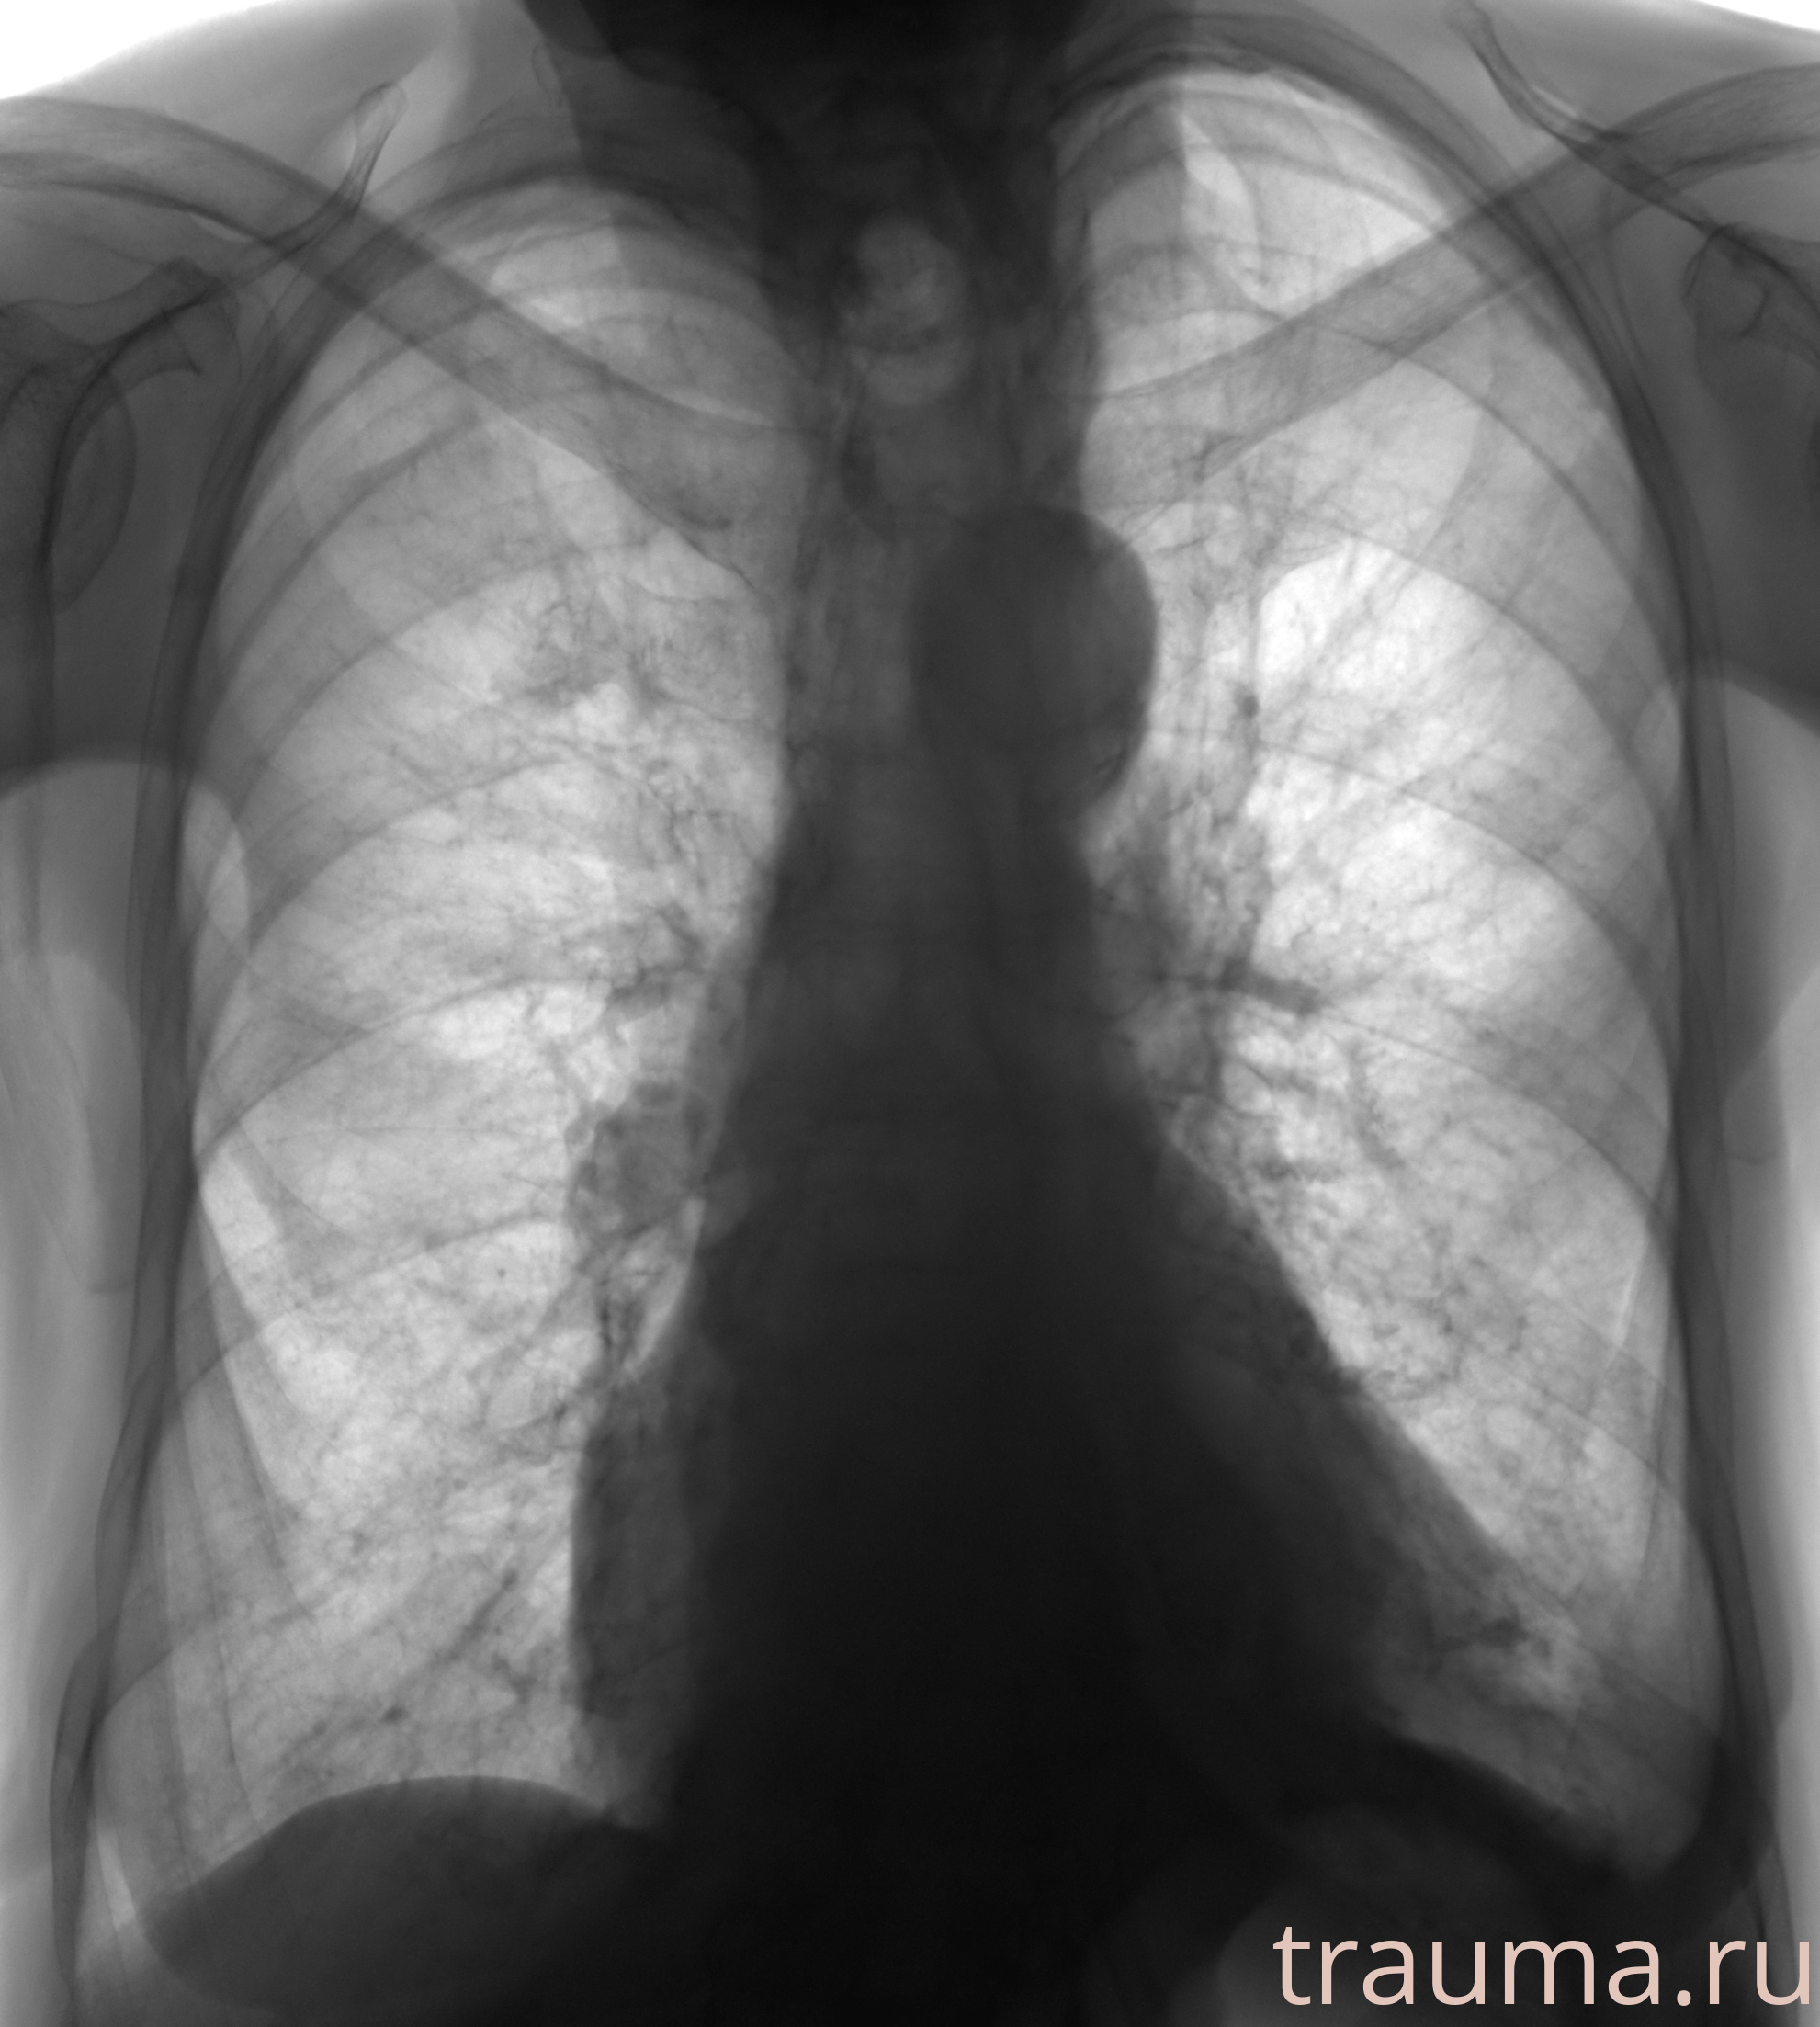

Рентген на дому: по вашему адресу приезжает врач-рентгенолог, травматолог-ортопед с мобильным рентгеновским аппаратом, проводит диагностику травмы или заболевания, делает необходимые рентгенограммы, дает рекомендации по дальнейшему лечению. Получить качественные снимки в домашних условиях возможно благодаря уникальной методике, разработанной МосРентген Центром для института  Склифосовского